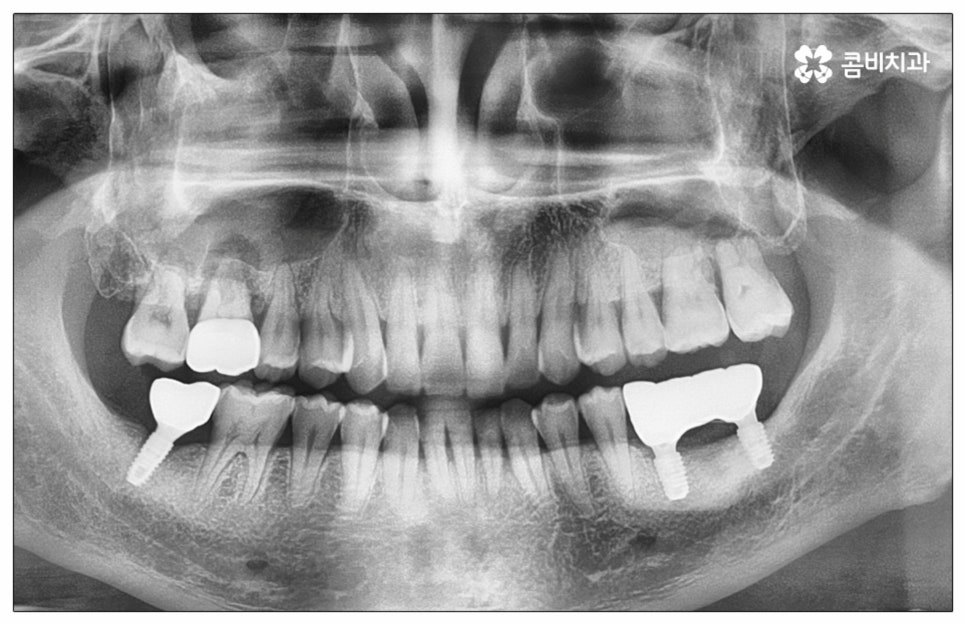

예전에는 이런 상황에서 틀니를 많이 이용하였으나 저작력 회복이 본래 자신의 치아 대비 20~30% 정도 밖에 되지 않고 잦은 탈락 위험 및 이물감, 잇몸을 눌러 장기적으로 잇몸뼈가 내려앉을 수 있다는 점 등 여러 가지 불편함이 있어 요즘은 임플란트 시술을 선호하시는 분들이 더 많아지고 있어요. 임플란트란 인체에 무해하며 잇몸뼈와 잘 결합하는 인공 치근을 잇몸뼈에 직접 식립하고 그 위로 기둥이 되는 중간 지대주와 치아 머리가 되는 크라운 보철물을 연결하여 인공 치아를 만들어 주는 시술을 말하는데, 자연 치아의 80% 정도 저작력 회복이 가능하기 때문에 식사를 할 때 음식을 크게 가리지 않아도 된다는 점 그리고 심미적으로 봤을 때 주변 치아와 자연스럽게 어우러진다는 점 때문에 각광을 받고 있습니다. 게다가 건강 보험 가입자이면서 만 65세 이상 부분 무치악 환자라면 평생 임플란트 2개까지 보험 적용을 받아 비용 부담을 줄일 수 있기 때문에 더욱 더 수요가 늘어나 이제는 치아 상실에 대체하는 대표적인 방법으로 임플란트 시술이 꼽히고 있는데요.

많이 대중화 되었다고 해도 임플란트 수술 자체가 술자의 숙련도에 크게 영향을 받는 복잡하고 고난도의 진료인 것은 틀림이 없기 때문에 담당 의료진이 해당 분야 임상 경험이 풍부한지, 뛰어난 기술력과 노하우를 가지고 있는지 꼼꼼하게 체크해 보실 필요가 있어요. 특히 노년층의 경우 당뇨, 고혈압 등 만성 질환을 앓고 있는 경우가 많아 혹시 상시 복용하고 있는 약이 있는지, 현재 환자 개개인의 상태는 어떤지, 사전 처치가 필요한 부분은 없는지 등등 수술 조건을 좀 더 까다롭게 평가한 후 환자분들과 이에 대해 충분히 상담하고 맞춤형 치료 계획을 세워 진행해야 하며 이를 위해 3D CT 와 같은 디지털 검진 장비를 통해 구강 내부 구조를 면밀하게 살피고 방대한 임상 데이터를 축적한 정품 임플란트 재료를 이용하여 연령이나 회복 정도를 살펴보면서 체력적 부담을 줄이는 방향으로 무리하지 않게 식립하는 것이 무엇보다 중요하다고 할 수 있습니다.

이때 추가 수술은 비급여 항목으로 건강보험임플란트 대상에서 제외되니 이에 대해서도 꼼꼼하게 살펴보시고 정밀 검진 후 담당 의료진과 자신의 상황에 대해서 충분하게 상담해 보시길 권유드리고 있습니다. 추가 수술의 대표적인 예로는 뼈이식 수술이 있는데요. 이것은 임플란트를 식립할 때 바탕이 되는 잇몸뼈의 높이나 폭, 밀도 등이 부족하다면 먼저 이를 보충해 주고 나서 임플란트를 심어주는 과정을 의미하며 같은 이유로 식립 성공률이나 장기적인 안정성을 높이기 위해 꼭 필요한 사전 처치, 즉 상악동 거상술 및 치주 질환 관련 수술 등을 먼저 해야 한다면 이 역시 추가 수술의 범주로 들어가니 자신의 상황에 대해서 상세하게 알아보실 필요가 있어요.